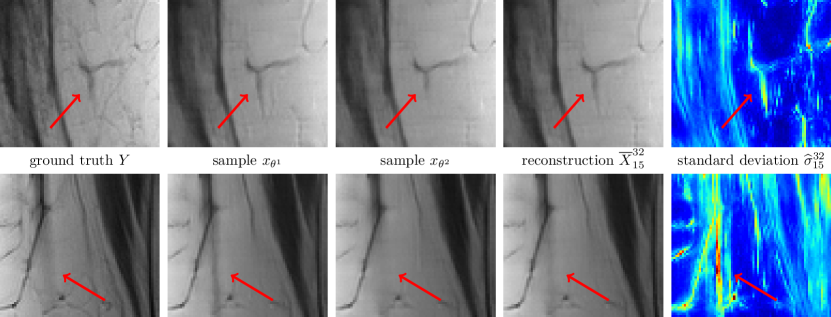

Figure 6 shows the multi-coil reconstruction results for 888-fold undersampling and both data sets in the same arrangement as before, the entropy level is H¯(Σ)=31.41¯𝐻Σ31.41\overline{H}(\Sigma)=-31.41. As expected, the overall reconstruction quality is quantitatively and qualitatively inferior to the case R=4𝑅4R=4. As before, the difference of the deterministic and the stochastic restored images is relatively small and the standard deviations properly identify regions with higher uncertainties. Finally, Figure 7 depicts zooms of two different MRI reconstructions (R=4𝑅4R=4, PD), in each row the ground truth, two realizations, the stochastic reconstruction and the standard deviation are visualized. The regions highlighted by the arrows indicate structures and patterns that differ among various samples. The variability of the single realizations can be interpreted as hallucinations, which are properly detected in the corresponding standard deviations. This empirically validates that our proposed method to measure the standard deviation actually quantifies the magnitude of the model-related uncertainty. Figure 8 contains a visual comparison of our method with selected competitive methods from the fastMRI leader board. As a result, both E2EVN [42] and iRim [38] achieve slightly superior quantitative results at the expense of significantly more learnable parameters. In a qualitative comparison, we observe that our proposed method is capable of retrieving fine details, only the signal of a few high-frequency patterns is lost. Finally, U-Net [23] results are inferior to the considered competitive methods – both quantitatively and qualitatively.

Figure 7: Zooms of multi-coil MRI reconstruction (R=4𝑅4R=4, PD). From left to right: ground truth, two distinct samples, stochastic reconstruction and standard deviation (00 Refer to caption 0.030.030.03). The arrows highlight patterns that are only visible in distinct samples.